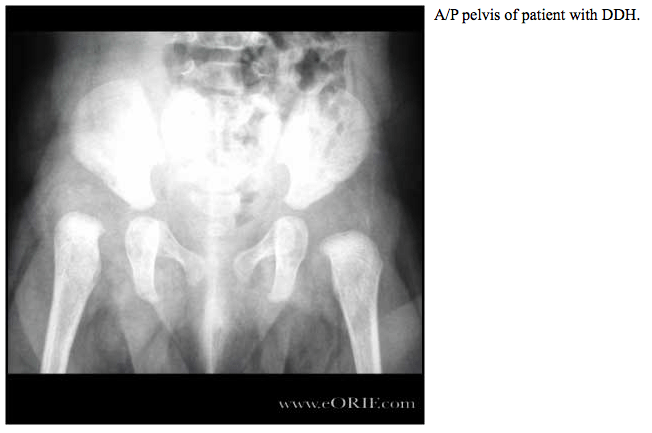

Developmental Dysplasia

This is necessary to make the diagnosis or to be sure the hip is normal. Developmental dysplasia of the hip occurs when the baby’s hip socket is too shallow to cover the head of the thigh bone. Most people with hip dysplasia are born with the condition. Surprisingly, approximately one in four had developed dysplasia that was treated with bracing..

This is necessary to make the diagnosis or to be sure the hip is normal. Developmental dysplasia of the hip occurs when the baby’s hip socket is too shallow to cover the head of the thigh bone. This test attempts to detect joint subluxation or dislocation by trying to displace the femoral head posteriolaterally from the acetabulum. If a hip.